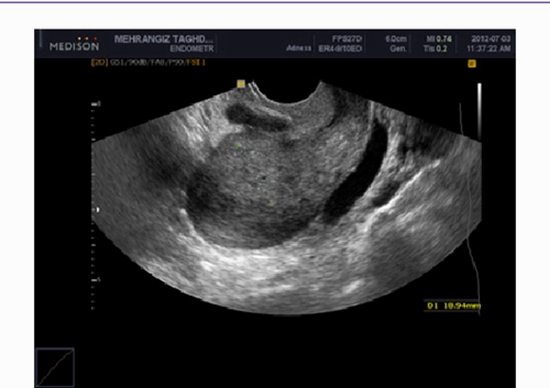

Totally, 280 patients who were referred for TRUS guided biopsy of the prostate were divided randomly into two equal groups. The case group received an intrarectal mixture of povidone-iodine and lidocaine gel before performing biopsy, while the control group received only lidocaine gel. Patients were followed up for 30 days for possible signs of infection including fever, chills and dysuria.